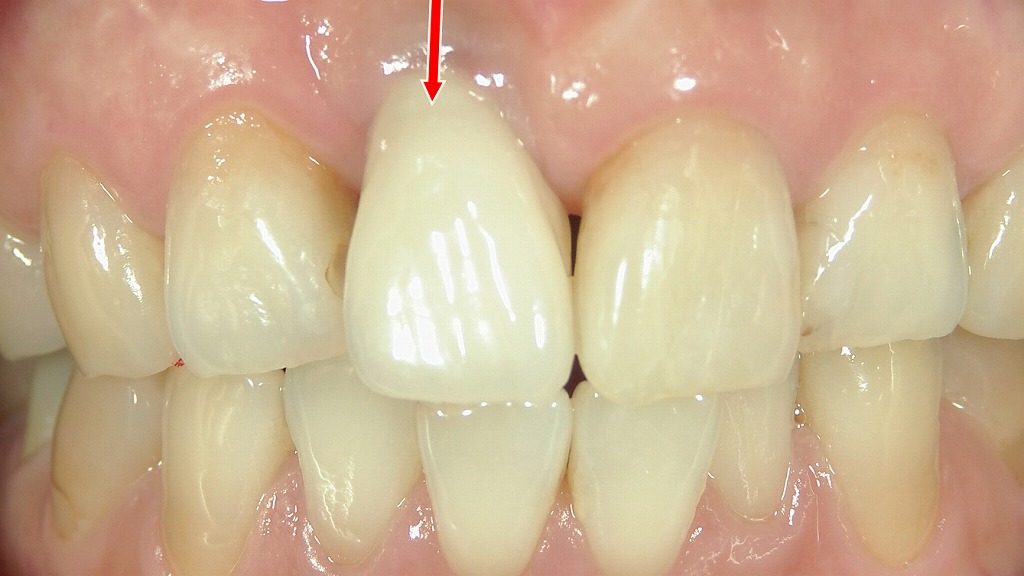

■ 右上前歯部の骨幅不足:インプラント前に骨造成が必要な状態

この咬合面観の写真は、右上顎1番の欠損部を上から観察した状態です。欠損部の歯槽堤は中央がくびれた形態となり、頬側から舌側(頬舌方向)の骨幅が明らかに不足している所見が確認できます。

赤い矢印の方向に示されるように、歯槽堤の厚みが非常に薄く、インプラント体(通常直径4.0mm前後)の安全な埋入に必要な骨幅(約6〜7mm)が確保できていない状態です。このままインプラントを埋入すると、頬側骨が破裂したり、インプラントスレッドが露出するリスクが高くなります。

さらに、歯槽堤の形態は突出感が少なく、**薄い歯肉形態(Thin biotype)**が疑われ、審美領域でのインプラント治療では歯肉退縮の懸念もあります。

■ 治療上のポイント

- 骨幅不足 → GBR(骨造成)が必須

インプラント直径を許容するためには、補填材と膜を用いた水平的GBRが必要になる可能性が高い。 - インプラント埋入ポジション確保が難しい

骨幅が不十分なまま埋入すると、頬側に薄い骨しか残らず、長期予後に問題が生じる。 - 歯肉退縮への配慮が重要

前歯部インプラントでは、審美性を確保するために**結合組織移植(CTG)**で軟組織のボリュームを補うことも検討される。

■ インプラント最終補綴の装着:自然な前歯の形態と色調を再現

この画像は、右上顎1番のインプラントに最終上部構造(セラミッククラウン)を装着した後の正面観です。赤い矢印が示す中央の前歯がインプラント補綴物です。

インプラント治療前は、

- 骨幅の不足

- スレッド露出

- 大規模なGBR(自家骨+人工骨+メンブレン)

を必要とした症例ですが、最終補綴物が装着される段階では、隣在歯と調和した自然な形態・歯肉ラインが再現されています。

画像からは以下の特徴が確認できます:

- 左右対称性のある形態

隣の天然歯と比べても、歯冠の大きさ・縦横比が自然に整えられている。 - 歯肉の安定

GBRによって確保された頬側骨が歯肉の支えとなり、退縮が見られず良好な歯肉ライン。 - セラミックの透過性・色調が天然歯に近い

全体的に調和したシェードで、違和感の少ない審美性が確保されている。 - 噛み合わせも適正に調整

咬合面からみても前歯のガイドに無理がなく、機能性も確保されていると考えられる。

審美領域のインプラント症例として、骨造成~最終補綴までの治癒・設計が良好に進んだ結果が反映された仕上がりとなっている。